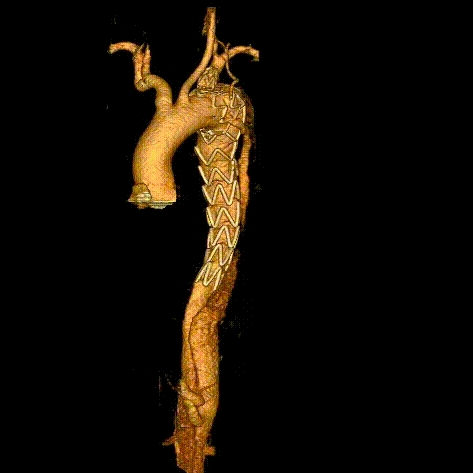

术前CTA:主动脉弓、左锁骨下动脉、胸主动脉附壁血栓伴部分穿透性溃疡。病变位于左锁骨下动脉根部前壁位置,近端锚定区不足

术前CTA三维重建

术后结果:主动脉弓穿透性溃疡隔绝良好,无内漏;分支支架通畅,形态良好;椎动脉供血良好。

术后结果:近端Ia型内漏消失,椎动脉无栓塞,LSA开口稍狭窄,血流通畅。

术前CTA:B型主动脉夹层破裂,左侧胸腔大量积血、积液,双肾萎缩

术后结果:主动脉夹层破口隔绝,可见少量延迟内漏,分支支架血流通畅。